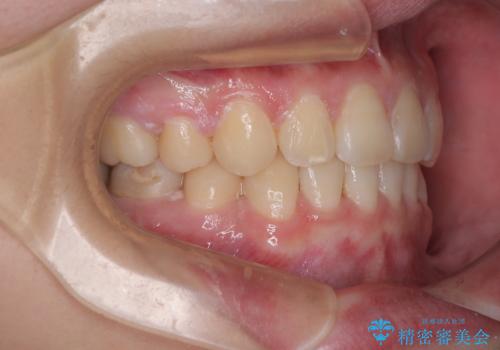

- 矯正装置

- クリアブラケット

- 転勤により東京へ移られることになり転院先を探されていた患者様です。ワイヤー矯正の途中での急な転勤なうえ、今後2~3年以内に再度転勤になる可能性もあるというご事情でした。

そのため、限られた期間内に効率よく治療を完了するために、「抜歯スペースの確実な閉鎖」「深い噛み合わせ(過蓋咬合)の改善」の2点を主軸とした治療計画を立てました。

結果的に1年半で、再度転勤になる前に治療を終えることができました。